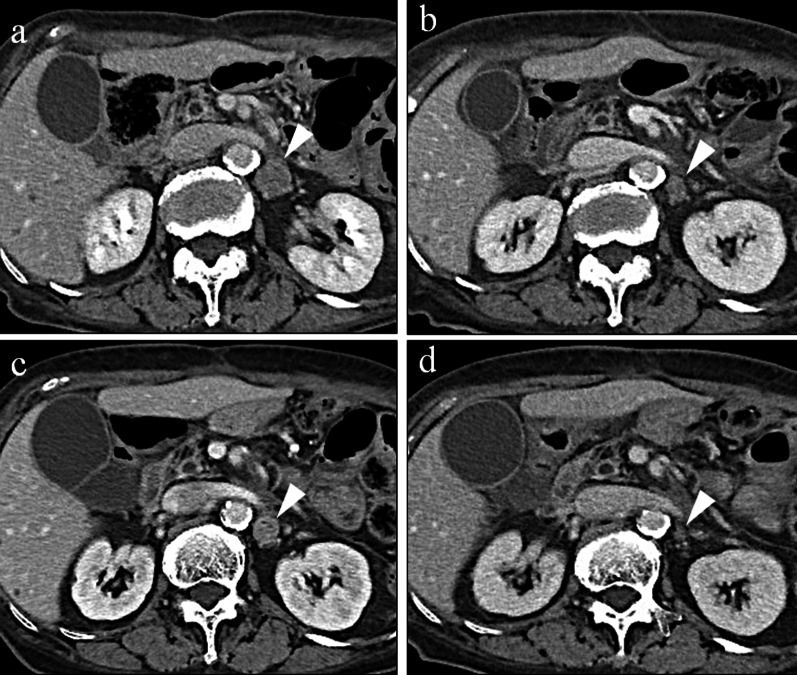

Fig. 4.

a Recurrent No. 16b1 enlarged to 20.1 mm after SOX therapy. b Lesion shrank to 15.6 mm after three courses of RAM + PTX therapy. c Lesion enlarged to 18.1 mm during the first RAM withdrawal period. d Lesion again shrank to 10.5 mm with resuming RAM administration.

One year after gastrectomy, a CT scan revealed swelling of the paraaortic (No. 16b1 LN) (Fig. 3a) and left supraclavicular LNs. In addition, CA19-9 remained high at 40.1 U/mL, CEA elevated to 6.1 ng/mL, and a positron emission tomography/CT scan showed abnormal accumulation of fluorodeoxyglucose in No. 16b1 LN (Fig. 3b). For the recurrent gastric cancer, S-1 plus oxaliplatin (SOX) therapy (S-1 80 mg/m2/day, oxaliplatin 100 mg/m2) was initiated as the first-line chemotherapy. After the seventh course of SOX therapy, the supraclavicular LN disappeared, but the paraaortic LN became enlarged (Fig. 4a). Therefore, PTX plus RAM therapy (PTX 80 mg/m2 and RAM 8 mg/kg) was initiated as the second-line regimen (Fig. 5). After three courses of PTX plus RAM therapy, CT revealed shrunken paraaortic LN (Fig. 4b), and PTX caused severe adverse effects, including grade 3 neutropenia and grade 2 peripheral neuropathy. The dose of PTX was reduced to 60 mg/m2 in the third course, and PTX was discontinued from the fourth course. CEA elevated to 11.2 ng/mL, but the size of paraaortic LN gradually shrank and CA19-9 decreased to 18.6 U/mL at the fifth course of RAM monotherapy. However, 3 + proteinuria and hypertension occurred before the sixth course of RAM monotherapy. The RAM was reduced to 6 mg/kg, and the patient observed a drug withdrawal period of 7 weeks. Because the size of paraaortic LN was enlarged after withdrawal period (Fig. 4c), 6 mg/kg of RAM monotherapy was resumed. After resuming RAM administration, the paraaortic LN significantly shrank again (Fig. 4d). However, 4 + proteinuria occurred and the urine protein–creatinine ratio was 5.29. Thus, RAM was withdrawn again, and regular CT and urinalysis were scheduled with sufficient informed consent. During the 14-month withdrawal period, hypertension was controlled by a calcium blocker, proteinuria remained at 2 + , and LN enlargement was not observed. Since the paraaortic LN was enlarged to 14 mm, RAM (8 mg/kg) was administered again. Unfortunately, the patient had a femoral fracture shortly after resumption and needed further drug withdrawal. During this period, the paraaortic LN grew to 14.8 mm. After the patient recovered, RAM was readministered, and the paraaortic LN shrank to 8.7 mm again. RAM monotherapy was continued while carefully observing adverse events, such as proteinuria and hypertension, 57 months after the conversion surgery.